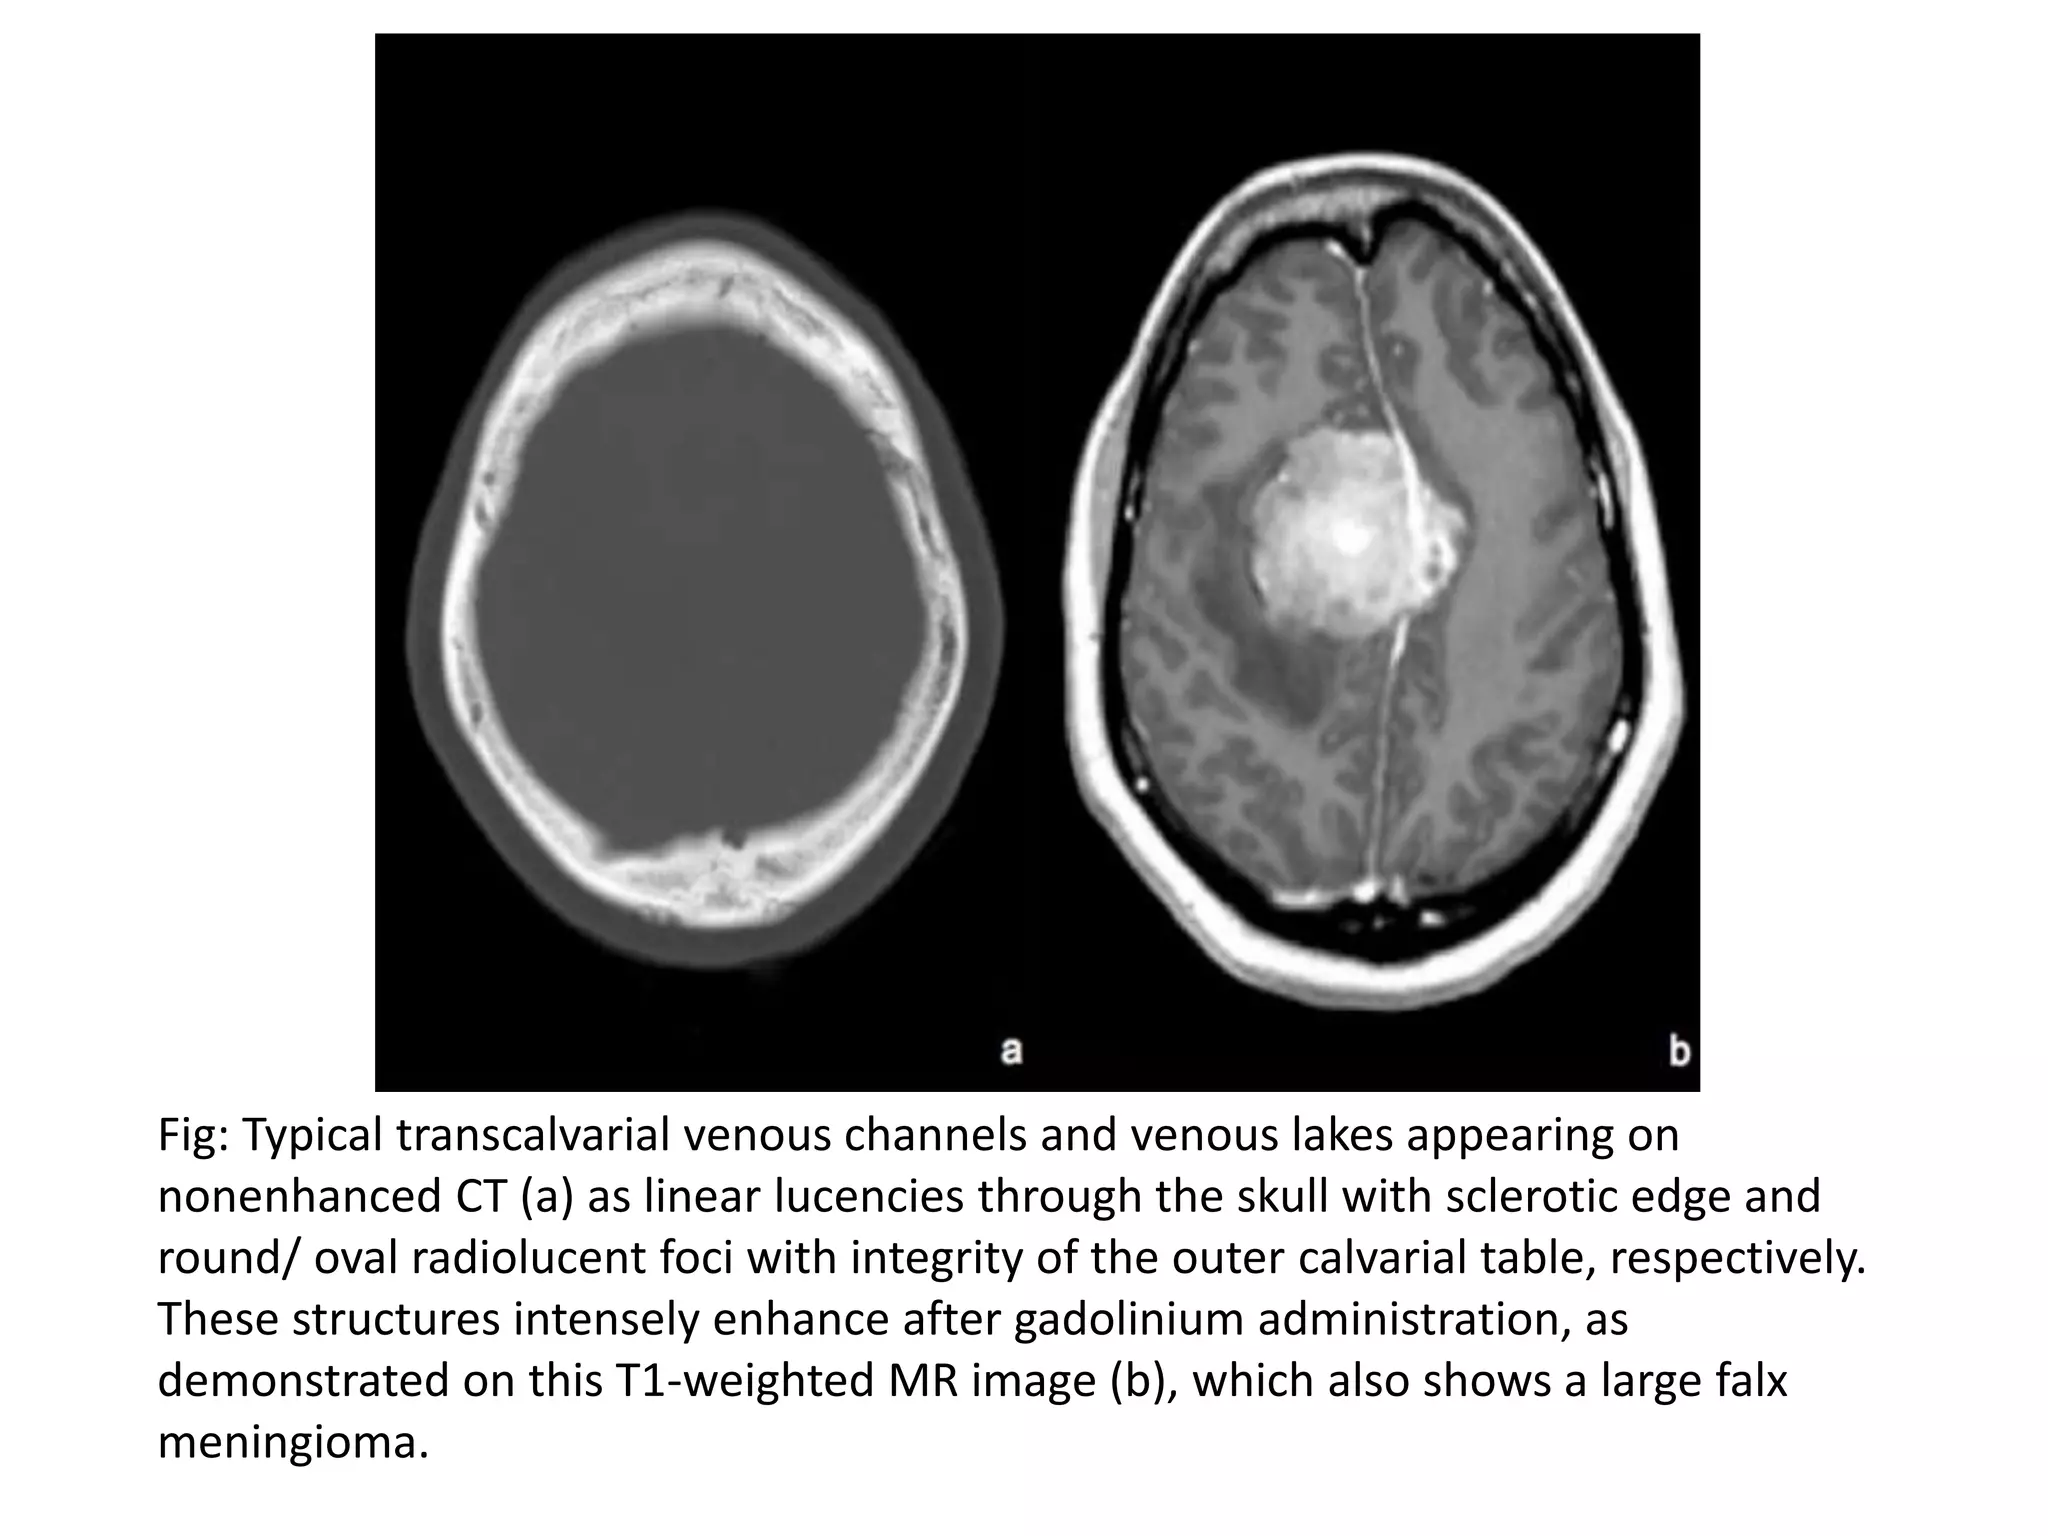

• Consist of apertures in the skull through which

emissary veins pass, connecting the venous sinuses of

the dura mater with veins external to the skull.

• Look like serpiginous or linear lucencies with sclerotic

borders through the skull, and are, therefore,

occasionally mistaken for sutures or fractures.

• Enlarged veins within the diploic space are known as

venous lakes, corresponding to round or oval lucent

foci, frequently along the inner table of the skull.

• These normal structures show an intense enhancement

after intravenous contrast administration on both, CT

and MR.

Fig: Typical transcalvarial venous channels and venous lakes appearing on

nonenhanced CT (a) as linear lucencies through the skull with sclerotic edge and

round/ oval radiolucent foci with integrity of the outer calvarial table, respectively.

These structures intensely enhance after gadolinium administration, as

demonstrated on this T1-weighted MR image (b), which also shows a large falx

meningioma.